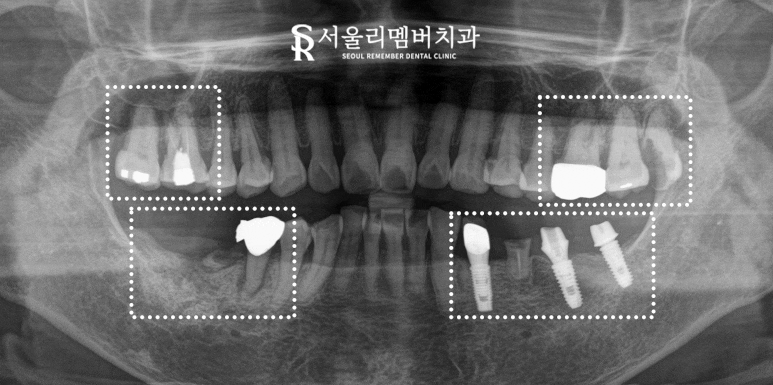

x-ray를 보겠습니다.

35번과 46번은 치근만 남아있고,

28번 사랑니는 절반이 썩어있으며,

16번은 신경치료 후 크라운을 씌우지 않아

치관의 마모가 크게 이루어졌습니다.

더불어 47번은 소실되어 있는데요.

이를 그대로 두면 어떻게 될까요?